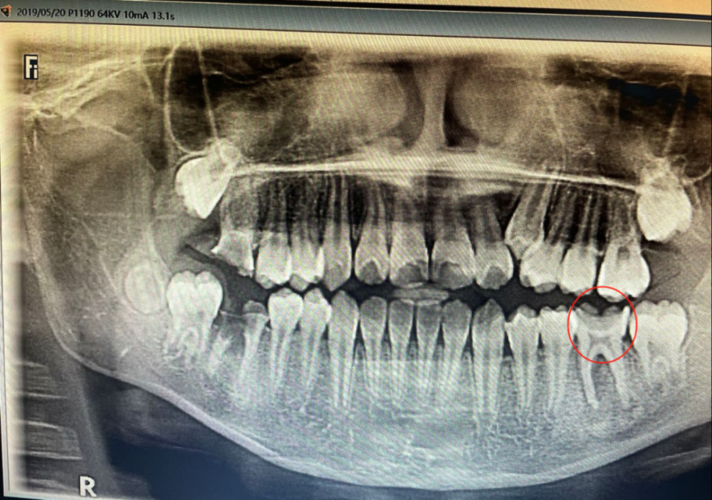

的口腔全景片显示,壮壮右下第一恒磨牙(也叫"六龄齿")牙根分叉已损坏

今天去医院拍了个六龄牙牙片,医生说牙根不行了,要拔掉再做治疗,我看

牙周病学根分叉病变

牙根分叉病变图片

根分叉